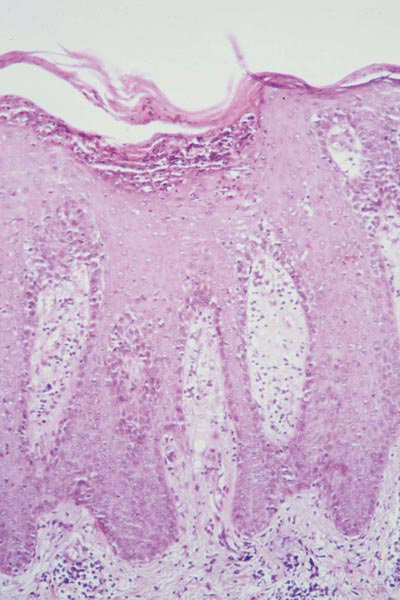

Les kératinocytes sont hyperprolifératifs, et le temps de renouvellement de l’épiderme est très accéléré. Cette prolifération accrue empêche le programme de différenciation des kératinocytes de se dérouler correctement et aboutit à la formation d’une couche cornée non complètement différenciée. Sur le plan histologique, les anomalies sont caractéristiques et associent: 1. Un épaississement de l’épiderme (acanthose) ; 2. un aspect festonné de la jonction épidermique avec des bourgeons interpapillaires très marqués ; 3. Une parakératose qui traduit le trouble de différenciation des kératinocytes ; 4. une infiltration par des neutrophiles.